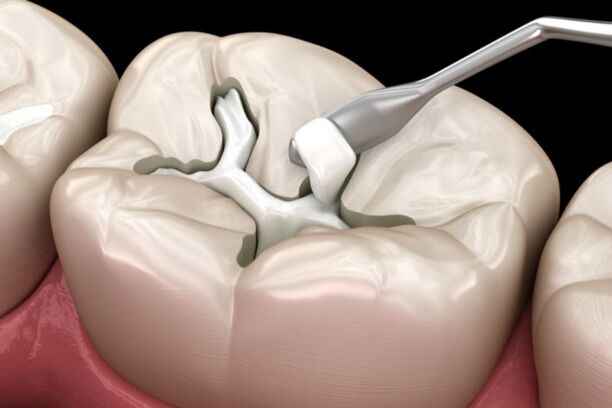

حشو الأسنان هو إجراء علاجي يهدف إلى إزالة الجزء المتضرر من السن نتيجة التسوس أو الكسر، ثم تعويضه بمادة حيوية تعيد للسن وظيفته وشكله الطبيعي. لا يقتصر الحشو على سد الفراغ فقط، بل يعمل على:

تمر عملية حشو الأسنان بخطوات دقيقة تضمن الراحة والدقة العلاجية، خصوصًا في مركز يعتمد معايير عالية مثل أضواء الحكمة. تشمل الخطوات:

- فحص سريري شامل لتحديد مدى التسوس وعمقه.

- تصوير شعاعي رقمي لتقييم الأنسجة الداخلية.

- تخدير موضعي مريح يضمن عدم الشعور بالألم.

- إزالة التسوس بعناية دون المساس بالأنسجة السليمة.

- تعقيم التجويف السني لمنع أي تلوث مستقبلي.

- وضع مادة الحشو بطبقات مدروسة.

- تشكيل الحشوة لتتوافق مع الإطباق الطبيعي.

- تثبيت الحشوة وصقلها للحصول على سطح أملس.

شرح خطوات حشو الاسنان خطوة بخطوة

تمر عملية حشو الأسنان بعدة خطوات أساسية لضمان دقة وراحة المريض:

- فحص شامل للأسنان واللثة بالأشعة الرقمية لتقييم التسوس وبنية الجذر.

- تنظيف التجويف وإزالة التسوس دون الإضرار بالأنسجة السليمة.

- تعقيم وتحضير السن لاستقبال مادة الحشو لضمان نجاح العملية.

- اختيار نوع الحشو المناسب حسب تشخيص الطبيب، مثل الحشوات الراتنجية أو السيراميكية.

- تطبيق الحشو بدقة على شكل طبقات متدرجة لاستعادة شكل ووظيفة السن.

- تشكيل وصقل الحشوة للحصول على سطح أملس ومتناسق مع الإطباق الطبيعي.

- التحقق من الإطباق والمضغ لتجنب الضغط غير المتوازن على الأسنان المجاورة.

- تقديم تعليمات متابعة للحفاظ على الحشوة ومنع أي مضاعفات مستقبلية.